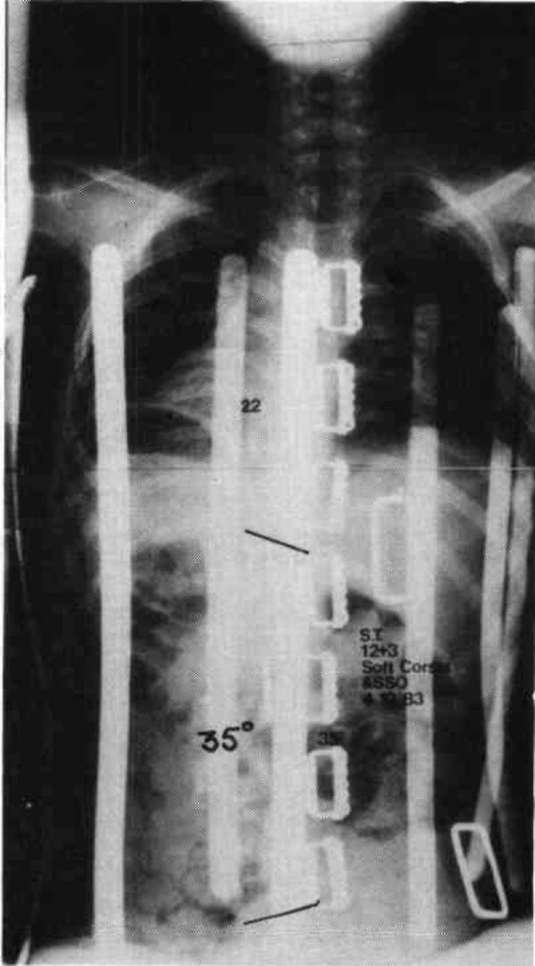

Let us now look at two examples were these stabilizing schemes have been simultaneously applied. Fig. 10a is a photo of a 12 year old boy with muscular dystrophy, sitting as he was presented to us. Fig. 10b shows the sitting support system properly applied. The corset is entirely independent; it is not attached to the seat. Fig. 10c and Fig. 10d compare his A-P spine x-rays without and with the orthotic system. The lateral tilt of his pelvis is reduced from 30 degrees to 14 degrees. The Cobb angle of his scoliosis was reduced from 65 degrees to 35 degrees. Curve control of this magnitude is not unusual as long as the deformity is still flexible. Fig. 11a is the x-ray of J.S., a 14 year old girl with cerebral palsy. She presented a right thoraco-lumbar scoliosis of 38 degrees and a rightward pelvic tilt of 8 degrees. Her shoulders were tilted 13 degrees to the left partly because she used her right arm for propping to avoid falling to the right. We provided her with a soft corset and the Gillette Sitting Support Orthosis. The Sitting Support Orthosis was to provide pelvic control and bilateral "propping" support. It had no head rest or anterior support. The x-ray taken just after fitting shows pelvic tilt reduced to 2 degrees (Fig. 11b), the Cobb angle of the scoliosis reduced to 22 degrees, and shoulders leveled. Both hands were free to function, and she said she could breathe deeper.

Figure 10c. A-P spine x-rays without the orthotic system.

Figure 10d. A-P spine x-rays with the orthotic system.